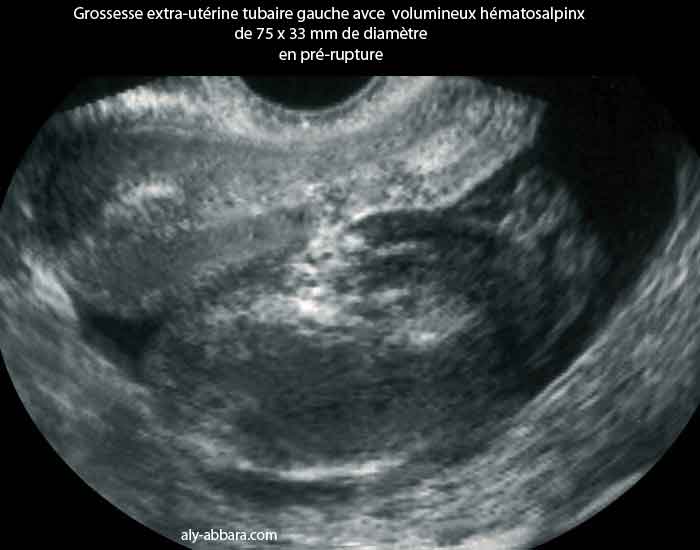

Grossesse extra-utérine tubaire : hématosalpinx volumineux en pré-rupture

Images échographique montrant un volumineux hématosalpinx de 75 x 33 mm de diamètre occupant le cul-de-sac postérieur, il s'agit d'une grossesse ectopique tubaire se manifestant par des métrorragies provenant au moment des règles (mais d'aspect noirâtre et d'abondance inhabituels) avec des douleurs pelviennes s'accentuant progressivement pour devenir, 3 jours plus tard, insupportables. Le dosage de hCG plasmatique, trois jours auparavant est de 1200 UI/l et au moment de la prise de cette image, est de 512 UI/L.

L'intervention chirurgicale réalisée 30 minutes après l'exploration échographique montre, un hématosalpinx gauche rompu sous forme de fissure totale et hémorragique de la paroi tubaire sur une longueur de 5 cm avec un hémopéritoine pelvien d'environs 200 cc. Il s'agit d'un véritable volcan en éruption.